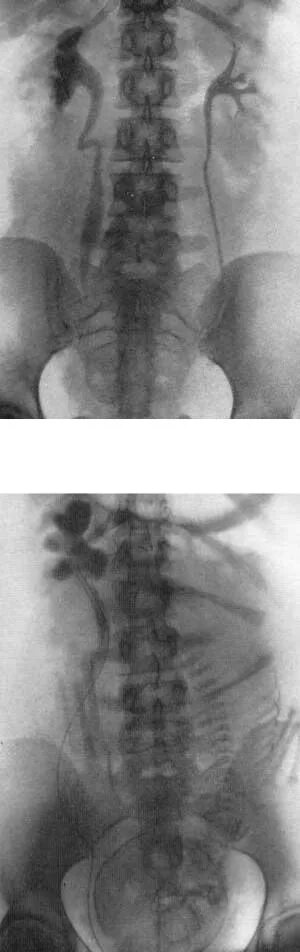

Псоас симптом